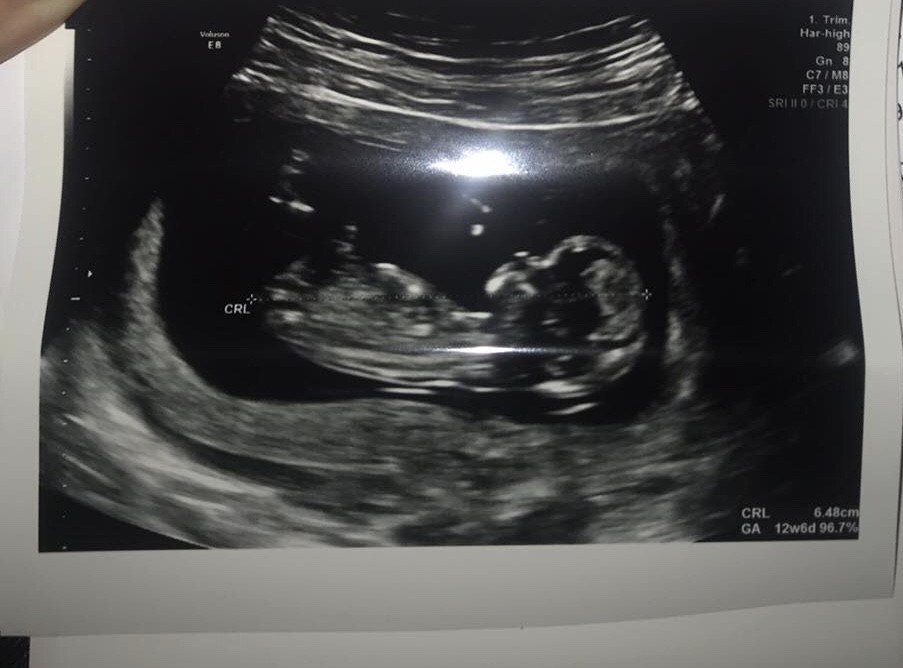

A dziękuje, wszystko dobrze, zdrowe jak ryba! Prawdopodobnie dziewczynkaTrzymam kciuki, odezwij się jak będziesz po wizycie![]()